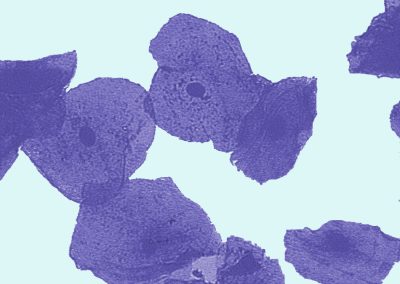

Biology Graphics (14-16)

Select the images you want and just save!

Thousands of images all created especially for education.